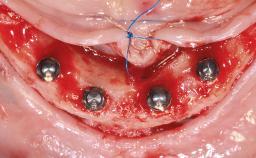

A 72-year-old male patient, partially dentate, presented with a request for a more functional and esthetic solution for his mandibular arch. He had lost his mandibular teeth over a period of more than twenty years due to a combination of periodontal disease and dental caries. He was not satisfied with his existing mandibular prosthesis, which was stabilized by his single remaining tooth 43. A pretreatment panoramic radiograph confirmed the absence of pathology. The patient was ambulatory, alert, and philosophical, and denied any health problems that would affect the dental treatment.